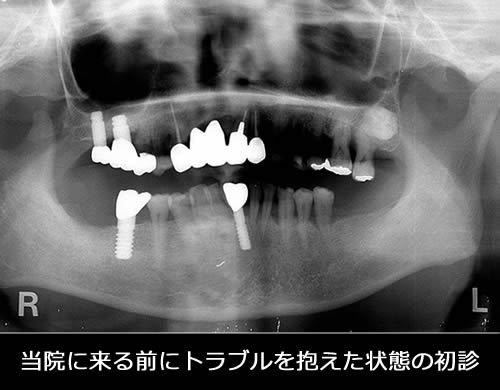

当院でリカバリーした患者さんをご紹介します。この患者さんは、他医院でインプラント治療をしたもののうまく噛めず、Dr.に相談しても取り合ってもらえず当院にいらっしゃいました。その後、当院で診断した結果インプラント治療だけではなく、全顎的に治療が必要と判断し咬み合わせを再構成する治療を行いました。患者さんとの約束である「前歯でトウモロコシを噛む」という公約も無事果たせて嬉しく思っています。

- 治療期間:26ヶ月

- 治療回数:155回

- 費用:インプラント治療:160万円 補綴治療:70万円

- リスク:メンテナンスを怠ると、インプラント周囲炎になる可能性があります。

- インプラント手術には合併症が伴う場合があります。

- 治療期間は治癒の状態により前後する場合があります。